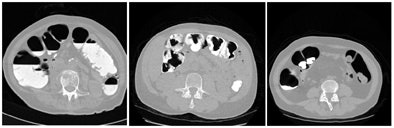

| The CTC appearance of the colon can vary widely depending on the administration of laxatives and fecal tagging, as exemplified by these three images. The image on the right also demonstrates how the appearance of the colon can vary dramatically between different colon segments: here, residual feces that are tagged clearly in ascending colon are not tagged at all in descending colon. |